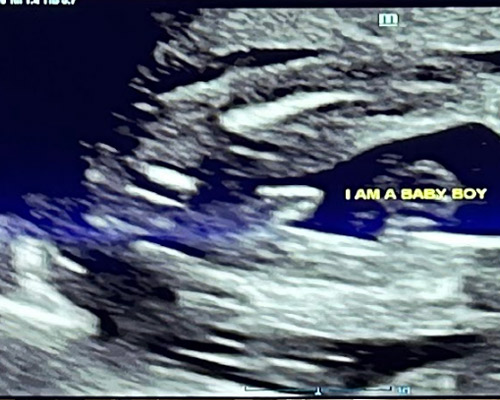

A gender scan near Wakefield is a specialised ultrasound used to determine whether you are expecting a boy or a girl. Many parents choose this scan to find out earlier rather than waiting for their routine hospital appointment.

During the scan, the sonographer carefully checks your baby’s position and uses ultrasound imaging to identify the gender as clearly as possible. Alongside this, you will also have the chance to see your baby moving, which adds to the experience.

- 2D ultrasound to determine your baby’s gender

From around 15 weeks, gender can usually be identified with a high level of accuracy, depending on your baby’s position during the scan.

The sonographer uses ultrasound imaging to examine the relevant area and determine whether you are expecting a boy or a girl.